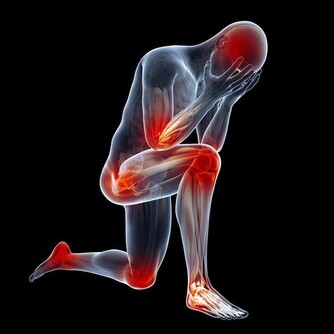

1臉色,眼白髮黃,有黃疸症狀的人需要養肝,肝臟不好的人,常

常表現為臉色,眼白或者皮膚發黃,即所謂的黃疸症狀需要護肝治肝.

2四肢乏力,容易疲倦,懶惰少動者需要養肝,這主要是因為,肝功能異常,碳水化合物,蛋白質,脂肪等的中間代謝障礙,導致能量產生不足,人體易疲勞,體力下降,精神欠佳,肝臟損害致使膽汁排泄不暢時,血液中的膽鹼酯酶減少,影響神經肌肉的正常的生理功能,因此當您出現了疲倦,不思飲食的症狀時就需要及時進行養肝調理

3脾氣暴躁,易怒,情緒容易激動的人需要養肝,肝臟喜疏惡鬱,經常生氣發怒,多因為肝氣淤滯不暢引起周身氣血運行紊亂,其他臟腑器官受干擾而導致的疾患發作,雖然一時可能不會出現什麼症狀,不過確實會給我們的肝臟健康埋下不少的定時炸彈,因此,經常生氣,煩躁,情緒波動,腹部脹滿的人需要及時進行養肝調理

4厭油膩,小便發黃者需要養肝,主要是因為肝臟分泌和產生膽汁的功能減弱,使得肝臟對脂肪的消化功能減弱,因此會出現厭油膩的現象肝臟排泄膽汁受阻,血液中的膽紅素升高,過多的膽紅素經過腎臟排泄,就會出現小便發黃的現象,因此,出現這一症狀的人應該注意養肝調理。